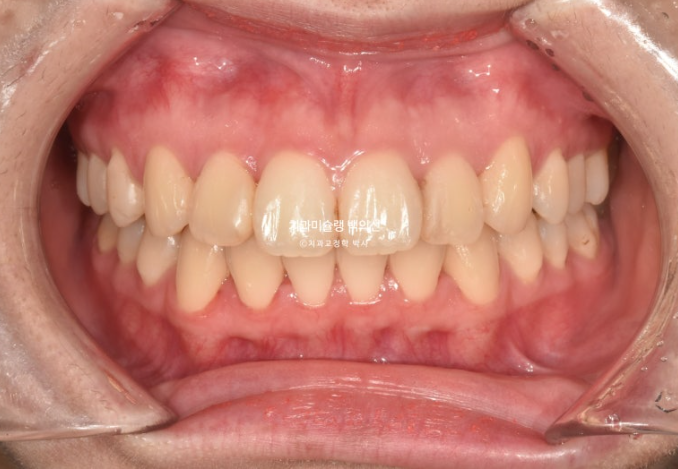

23년 7월 교정치료를 위해 내원한 20대 환자분입니다.

오래 전 비발치교정을 했던 이력이 있습니다.

앞니는 가지런한 편이며 중심선도 거의 맞습니다.

교합은 좋은 상태이고

치열도 꽤 가지러한 편입니다.

입안 사진만 보면 재교정을 왜하나 싶겠지만 환자분이 재교정을 해서라도 고치고 싶은 것은

돌출입

거미스마일 입니다.